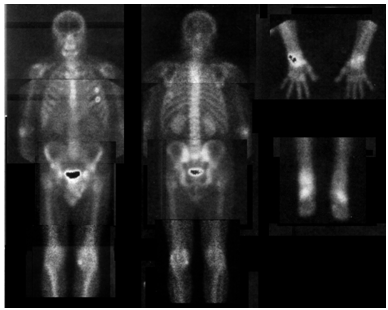

The patient was thoroughly followed up. In 2008, the patient was examined in a state of complete clinical remission. Osteoscintigraphy revealed almost complete normalization of the radiotracer accumulation in the joints (Figure 3) (Table 1). The AI of the right elbow decreased by 30% compared to the previous study, AI of shoulder joints decreased by 30%, AI of the right ankle by 43%, tarsal joints-47%.

Figure 3 Osteoscintigraphy with TC-99m labeled sodium pyrophosphate (16.09.2008).

In the presented case we observed opposite dynamics of intestinal and articular manifestations of Whipple's disease that was confirmed not only by clinical, laboratory data, but by the results of quantitative scintigraphy. Osteoscintigraphy with the calculation of AI in the joints can be an important quantitative method for objective assessment disease activity of the joints and it may be used to confirm the effectiveness of the treatment in Whipple's disease.